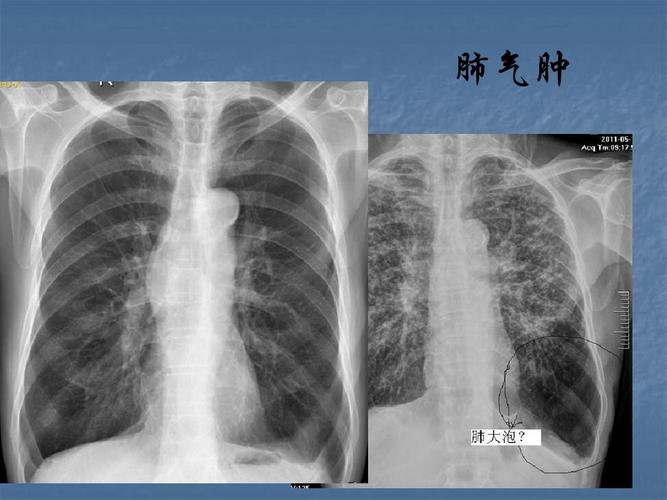

肺气肿胸片典型图片

胸片图片肺气肿

肺气肿x线图片

肺气肿胸片